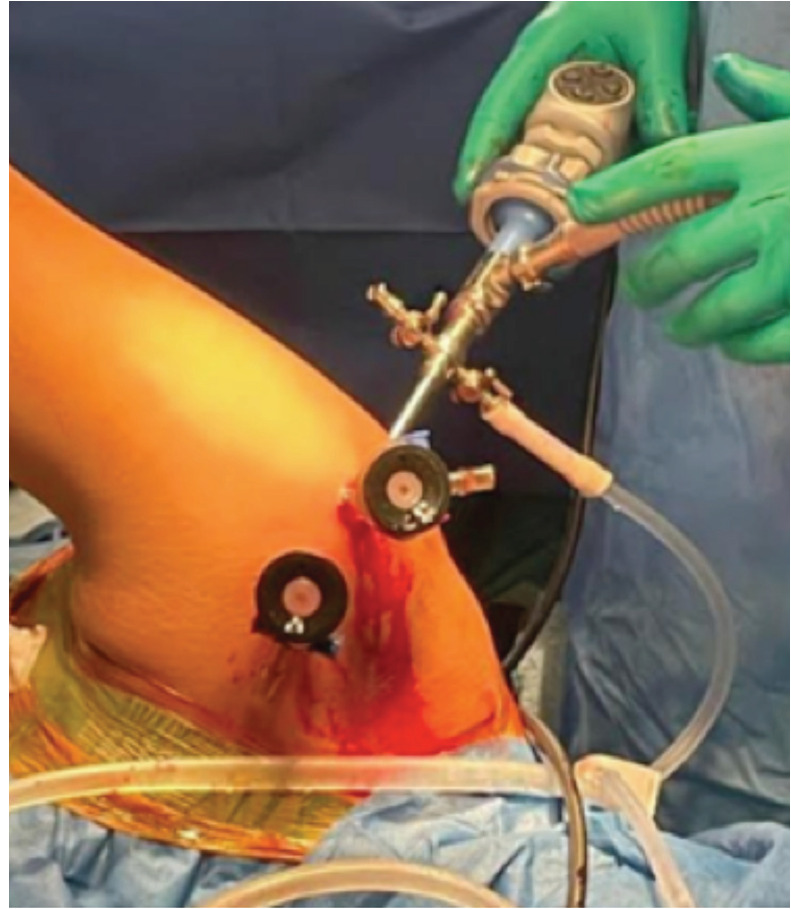

Materials and methods: A total of 36 patients underwent arthroscopic Bankart with Remplissage for recurrent anterior shoulder dislocation, enrolled between February 2022 to December 2023 considering various inclusion and exclusion criteria. Patients were evaluated in post op period for range of motion, oxford shoulder instability score and visual analogue score for pain at intervals of 6 and 12 months.

Results: All patients enrolled had soft tissue with bony Bankart lesion with mean of glenoid bone loss (%) was 11.75% (±3.15%) and all participants had engaging Hill-Sachs lesion. The mean pre-operative OSIS was 19.56 (±2.17) and mean VAS was 5.53 (±0.56). In the post op evaluation, there was no clinically significant decrease in range of motion with mean loss of external rotation of 3.86 (±1.44) at 12 months. The mean OSIS increased to 41.0 and mean VAS decreased to 2.36 at 12 months follow-up which was statistically significant. There was no incidence of dislocation in post op period of 12 months.